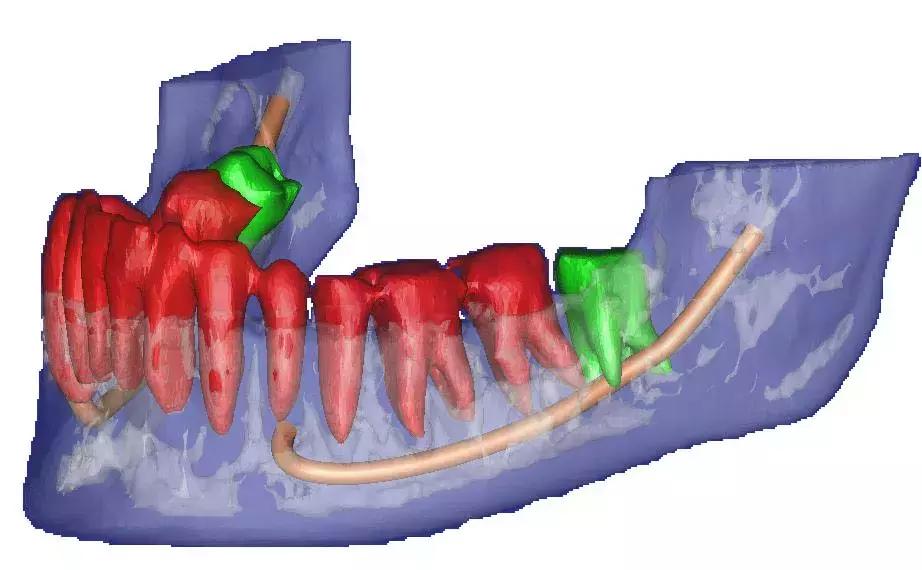

阻生智齿和神经的关系↓

对待这种「骑」在神经上的智齿要以医生建议为主,即使拔也一定要选择微创拔哦。这个危险距离,一锤子下去,神经可就很难保住了。